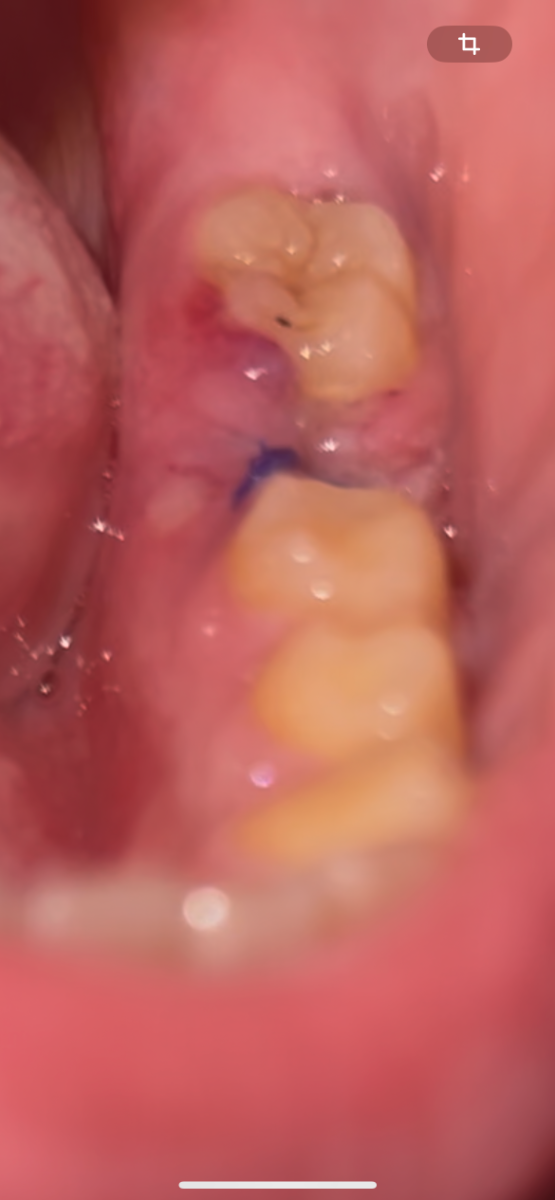

Георгий С Опубликовано 10 октября, 2024 Поделиться Опубликовано 10 октября, 2024 Здравствуйте, заранее извиняюсь за такое качество фото, сфоткал как смог. 3 дня назад удалили шестёрку, два дня было кровотечение, болело, пил Нимесил, потом отек десны, появился стоматит (вроде как он), все болит, есть нормально не могу, беспокоит эта отечность и боль. Таблетки по назначению пью. Что скажете? Ссылка на комментарий

Женька Опубликовано 10 октября, 2024 Поделиться Опубликовано 10 октября, 2024 Здравствуйте. 2 часа назад, Георгий С сказал: Что скажете? Скажу, что Вам надо показаться лечащему врачу. На представленном фото невозможно полностью оценить состояние лунки, хотя выглядит вроде бы неплохо. Но учитывая Ваши жалобы - лучшим решением будет показаться Вашему лечащему врачу. Возможно потребуется санация лунки. 1 Ссылка на комментарий

krokomot Опубликовано 10 октября, 2024 Поделиться Опубликовано 10 октября, 2024 Боль на 3й день после удаления может означать о начавшемся воспалении лунки вследствии ее инфицирования. Нужно обязательно посетить хирурга стоматолога. Ссылка на комментарий